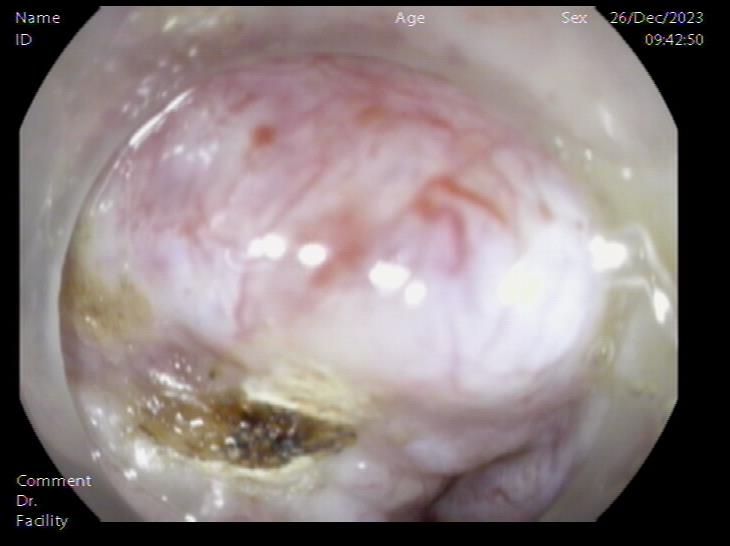

患者,66岁,女性,平素身体健康,以“发现胃肿物2年余”主诉入院,既往于外院行电子胃镜检查发现胃底隆起,直径约1.5-2.0cm,超声内镜检查考虑黏膜下来源间质瘤可能,不除外壁外病变压迫。外院CT提示胃底浆膜下囊性病变可能。患者及家属诊治心切,辗转数家医院后为求内镜下治疗遂来二附院。入院后在消化内科再次超声内镜检查,提示胃壁增生病变可能,增强CT提示胃底胃壁增厚,结合内镜检查。患者及家属强烈要求内镜下探查及病变切除术。术前在王进海主任的指导组织下,进行了专业组内及多学科讨论,与患者及家属充分沟通后,决定行内镜下切开探查及病变治疗术,必要时可行内镜-腹腔镜联合手术(LECS)。邹百仓教授带领内镜下肿瘤诊治及超级微创手术团队施行手术,术中逐层切开胃壁黏膜层及黏膜下层,暴露固有肌层,未发现胃壁病变,遂切开胃壁全层,局部腹腔探查,切口附近腹腔内似韧带组织上发现半球形隆起,表面透亮光滑,大小约1.5X1.5cm,术中请外科李军辉及袁庆攻教授会诊后确诊为囊性病变,讨论后建议可以观察或内镜切开引流,与患者家属沟通后家属强烈要求切开引流,遂用内镜切开刀切开囊肿,引流少量清亮囊液,囊肿塌瘪,观察囊肿切口及局部无出血,切除局部部分胃壁组织送检,内镜下严密关闭切口,留置胃管后,返回病房,常规对症治疗1周,患者无并发症发生,正常出院。

腹腔内囊肿 腹腔内囊肿近景

囊肿切开引流,囊壁塌陷 内镜下胃壁全层缝合